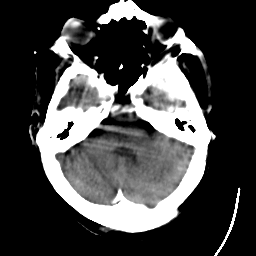

Meningioma: Roentgen-ray CT #1 -- Slice #4

[Home][Help][Clinical] Slice 4